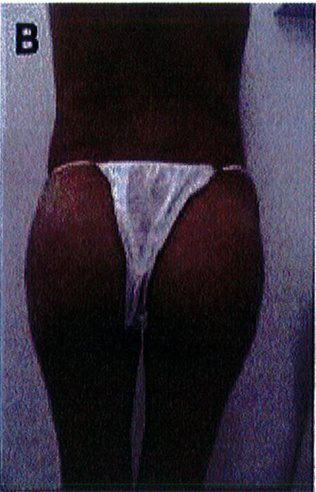

Để tránh tình trạng quá ngắn hoặc quá dài của vùng mông (hay còn gọi là mông dài/ngắn) thì tác giả đã kết hợp một phép đo đơn giản trước phẫu thuật, đo khoảng cách từ mào chậu phía sau tới đường ngang đi qua trung điểm nếp liên mông (khoảng cách A) và từ đường ngang đó tới nếp lằn mông (khoảng cách B) (Hình 1) đế tính vị trí chuẩn xác của khối im- plant.

Để tránh tình trạng phần mông trên được nâng lên quá mức, khoảng cách A thông thường phải gấp đôi khoảng B để có thể phù hợp cho nâng mông dưới cơ.

Nếu khoảng cách A ngắn hơn, nên sử dụng mặt phẳng trong cơ để tạo điều kiện cho khối im- plant được đẩy xuống thấp hơn 1 chút, giúp đạt được kết quả thẩm mỹ lý tưởng.

Hình. 1. Đánh giá trước phẫu thuật để lựa chọn bệnh nhân với mặt phẳng im- plant phù hợp.

Hình. 2. Bệnh nhân với khung chậu quá rộng hoặc quá ngắn đều không phù hợp với implant mông.

Hình. 3. (A-H) Tiền phẫu, chu phẫu và sau hậu phẫu 6 tháng của một bệnh nhân nữ 38 tuổi đươc ghép túi đôn mông với thể tích 330 cm3.

Hình. 4. (A-I) Hình ảnh tiền phẫu, chu phẫu và sau hậu phẫu 11 tháng của một phụ nữ 25 tuổi đã được thực hiện hút mỡ vùng éo, hông và sau xương vùng, đồng thời ghép khối cấy thể tích 270cm3.

Hình. 5. (A-F) Hình ảnh tiền phẫu và sau hậu phầu 4 tháng của bệnh nhân 67 tuổi, ghép khối implant thể tích 300 cm3.